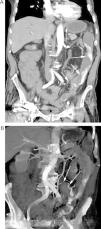

Paciente con HBD masiva en el postoperatorio de una reconstrucción de Hartmann. A) Reconstrucción coronal de TC en fase arterial tardía que muestra una extensa extravasación de contraste en el colon izquierdo (flechas). B) La reconstrucción «volume rendering» delimita el origen vascular del sangrado en una rama de la arteria mesentérica inferior (flechas).

Paciente con sospecha de HDB masiva. A) El estudio de angioTC muestra un sangrado activo en el bulbo (flechas). B) La reconstrucción MIP delimita el origen del sangrado (flecha gruesa) a través de ramas de la arteria gastroduodenal (flechas finas). C) La arteriografía guiada por TC confirma la extravasación de contraste (flecha), con posterior embolización selectiva.